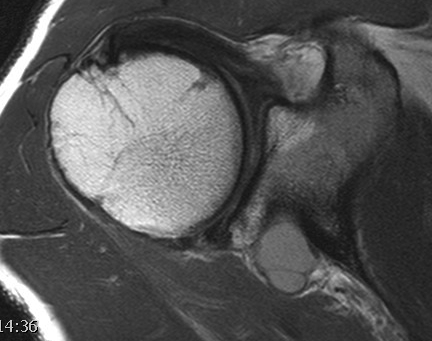

Spinoglenoid Cyst

MRI

Spinoglenoid cyst with SLAP tear and posterosuperior labral tear